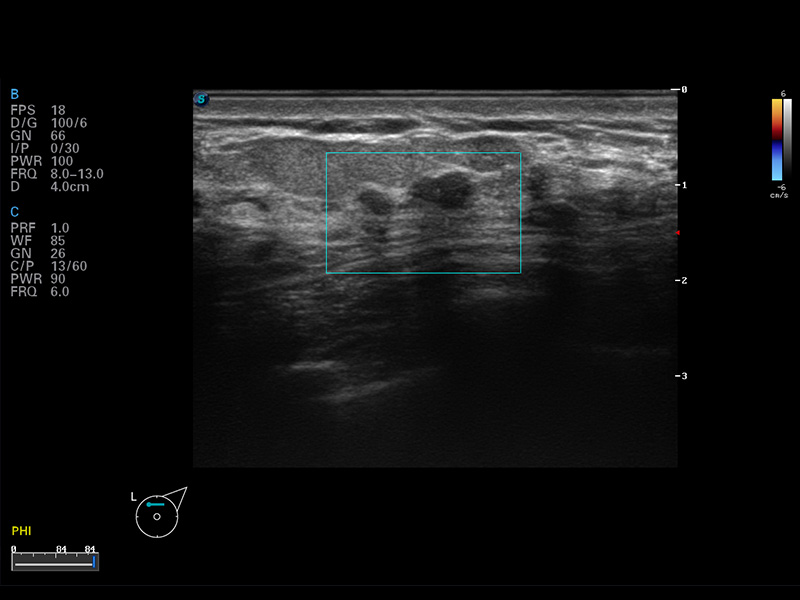

S8 EXP便携式彩色多普勒超声诊断仪是16877太阳集团研发的高端全身应用型便携彩超。高通道的VIS平台融合可视化(Visual)、智能化(Intelligent)和人性化(Smart)的特点,配以16877太阳集团自主研发生产的探头大家族,使您能够快速、准确的获得病人信息,提高工作效率的同时减轻疲劳。

μ-Scan微米成像

谐波成像

空间复合成像